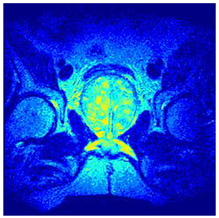

In this subsection, we will discuss the experiment designed to evaluate the performance of EO with cross-entropy for the segmentation of prostate MRI images. To this end, we use a group of reference images formed by a set of six prostate MRI images; see Figure 4. All the images from the group were extracted from the Ferenc Jolesz National Center for Image-Guided Therapy, Harvard Medical School, or Brigham Health Hospital datasets with no additional preprocessing [50]. Prostate MRI images are primarily used for disease diagnosis or to establish treatment for prostate-related diseases such as prostatitis, benign prostatic hyperplasia (BPH), and prostate cancer, among other diseases or medical conditions. In the context of this article, the images were used to test the efficiency of the equilibrium optimizing algorithm and compare it with the other six chosen algorithms. The segmentation of MRIs is carried out over four different thresholds levels: = 3, 4, 5, and 8. Due to the nature of the images, there was a limited number of different tissues in the images; thus, there was no point in evaluating a larger number of .

Figure 4.

Eleven transaxial-cut prostate MRI images. This figure presents a set of eleven transaxial-cut magnetic resonance (MR) images of the prostate. These images serve as the input dataset for evaluating the segmentation performance of the proposed algorithm.

Table 5 presents the segmentation of the MRIs using EO for a qualitative inspection. From Figure 5, it is clear that two lumps in the prostate have been highlighted by the thresholding process. Prostatic MRIs present noisy conditions, which makes it difficult to visualize the thresholding with the naked eye, so in Figure 5 we present the thresholded image as well as the histogram with the values of the thresholds generated by the EO. It can be observed in the histogram that the thresholds present an adequate distribution, even though this particular image has impulsive noise and a simple shape. Our findings indicate that four thresholds are typically sufficient for this application, which corresponds to identifying five different tissue types in the image. A smaller threshold value may result in a lack of sufficient contrast to highlight relevant anatomical structures, such as the prostate capsule. In contrast, a higher number of thresholds may lead to the incorrect differentiation of anatomical regions that should be connected.

Table 5.

Segmentation of transaxial-cut prostate MRI images Using EO and cross-entropy. This table presents the segmentation results of transaxial-cut prostate MRI images using the equilibrium optimizer (EO) and cross-entropy. Each row corresponds to a distinct MRI image, while the columns nt represent the number of thresholds applied during segmentation. The results illustrate the performance of the EO algorithm across different threshold levels for each image.